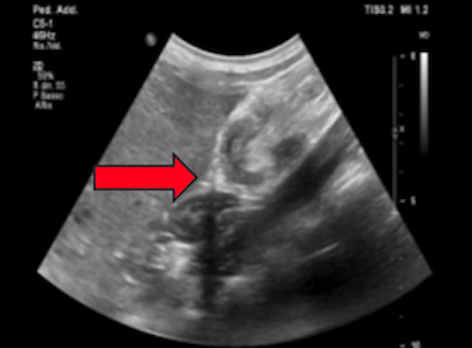

Bambino che ha sempre goduto di buona salute. All’età di due anni il piccolo lamenta un intenso dolore addominale, per cui viene condotto dai genitori in Pronto Soccorso pediatrico, dove all’ecografia addome viene evidenziata un’immagine a bersaglio in fossa iliaca destra, compatibile con un’invaginazione intestinale (IIA) (Figura 1).